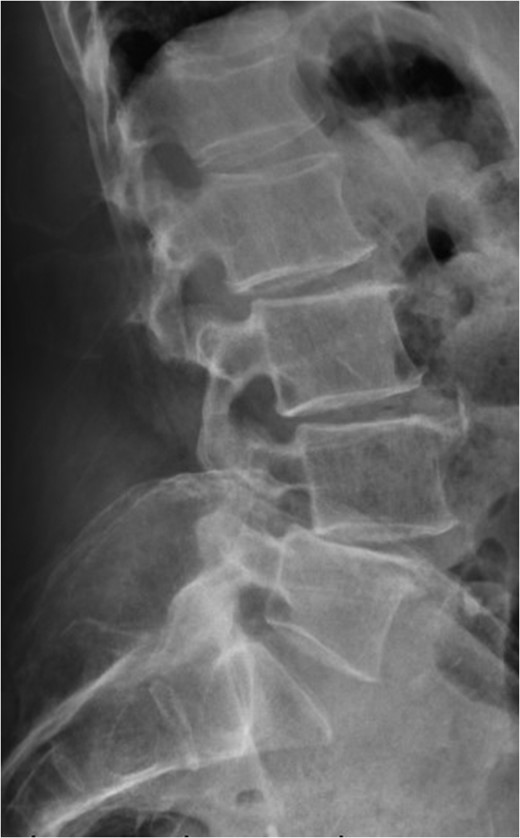

Standing neutral lateral lumbar radiograph obtained 17 months following the patient's L3–S1 laminectomy. The patient is now dealing with a Grade 1 anterolisthesis of L4 on L5, with a mild degree of retrolisthesis at each of the cranial levels depicted.